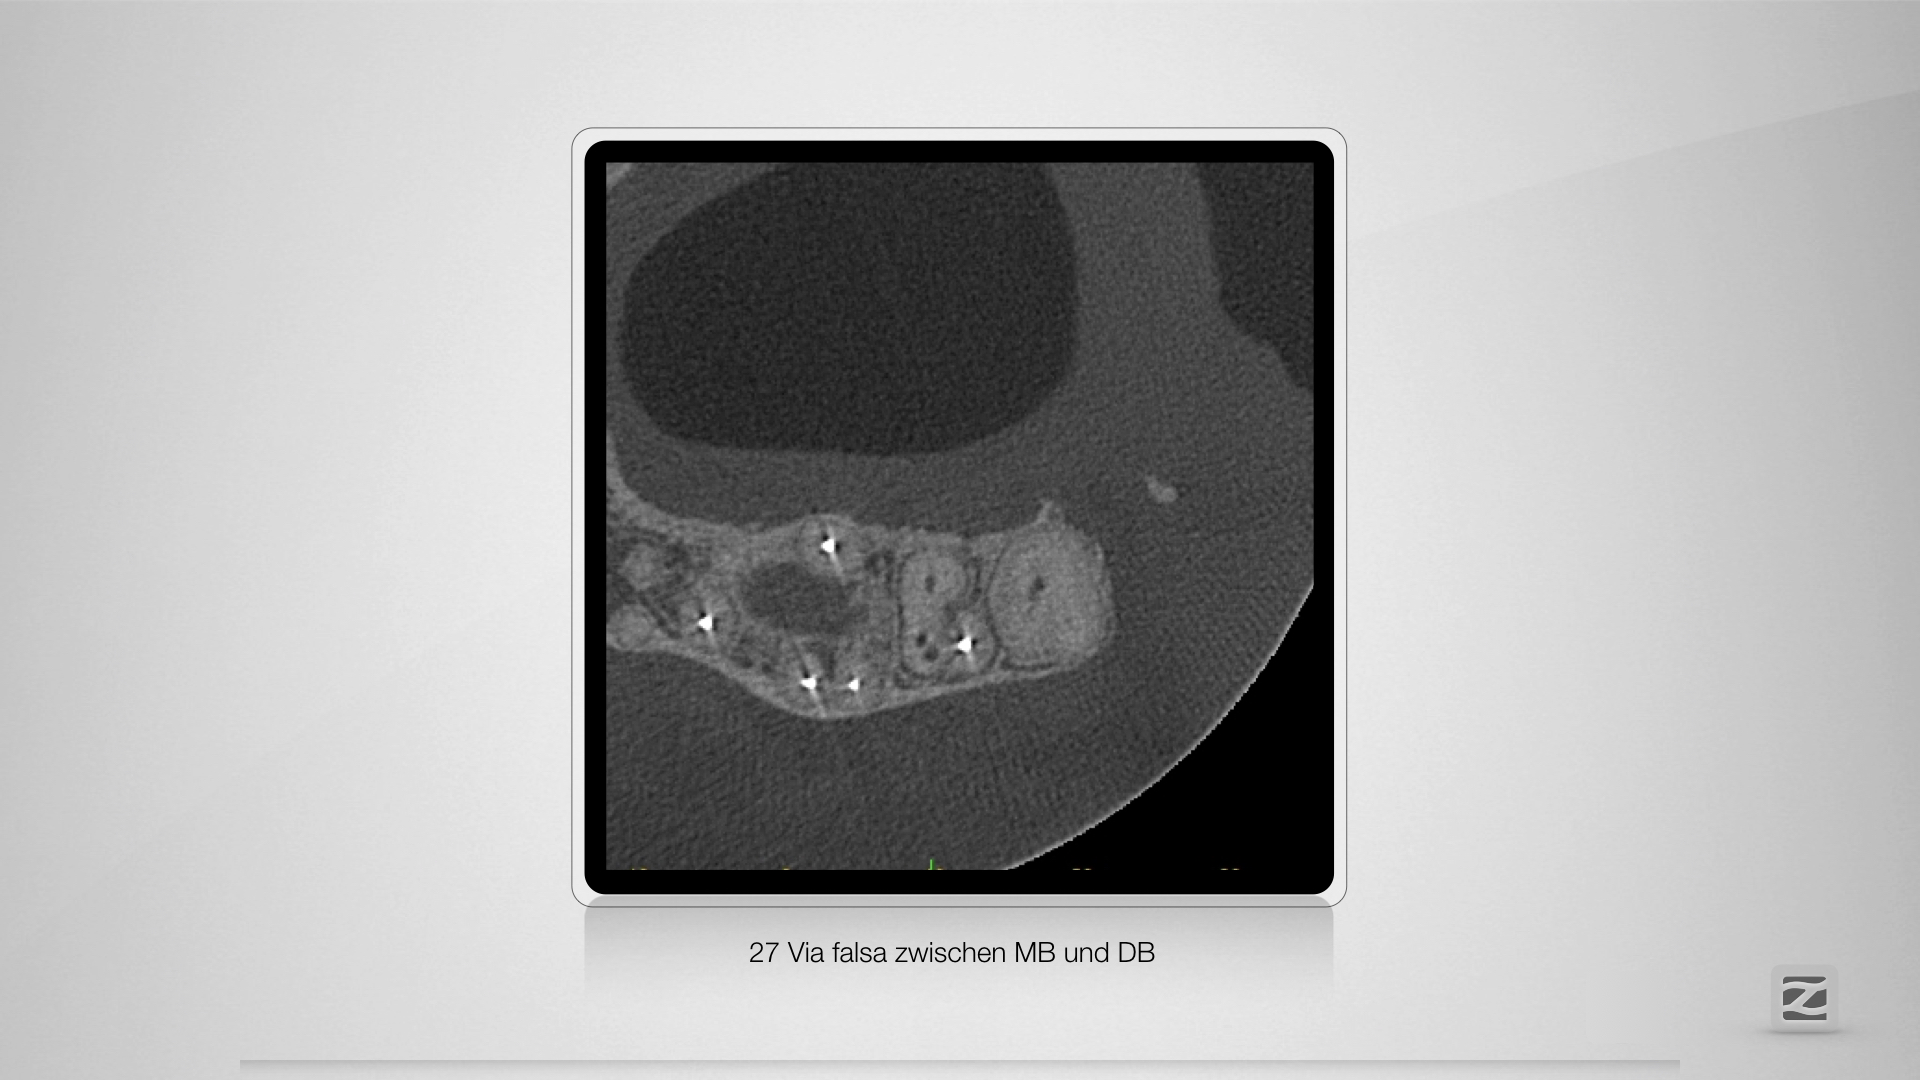

Fast getroffen ist auch vorbei!